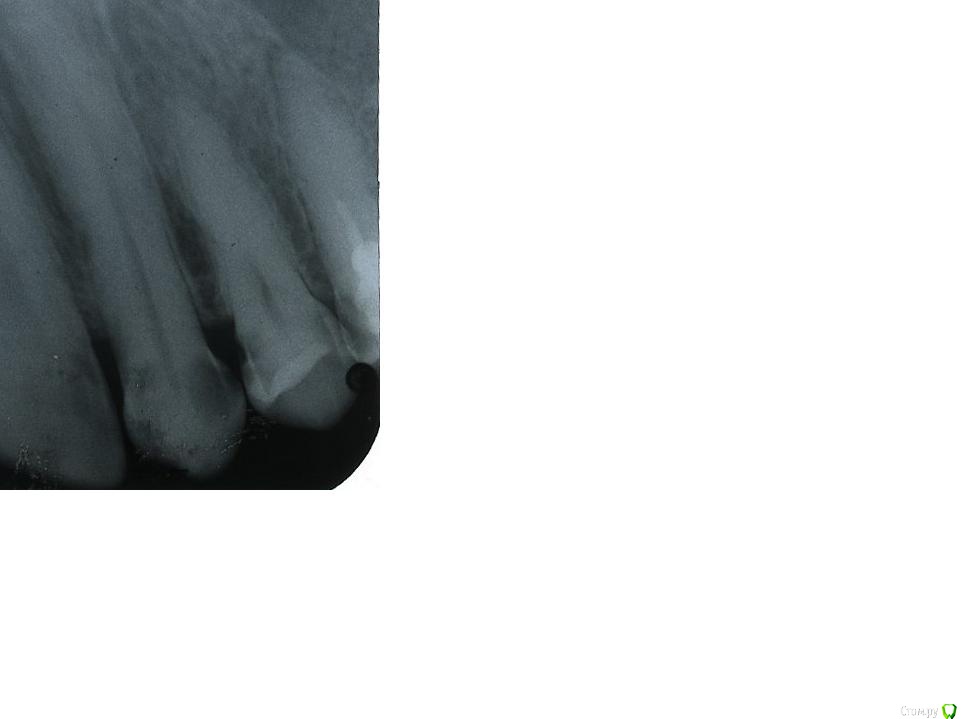

dann Опубликовано 25 февраля, 2018 Автор Поделиться Опубликовано 25 февраля, 2018 Рентген-снимок передних (передних справа) зубов Ссылка на комментарий

red_butler Опубликовано 26 февраля, 2018 Поделиться Опубликовано 26 февраля, 2018 Рентген-снимок передних (передних справа) зубовНа снимке три кариеса и один периодонтит, идите лечиться 1 Ссылка на комментарий

dann Опубликовано 26 февраля, 2018 Автор Поделиться Опубликовано 26 февраля, 2018 (изменено) Я так понял что первый слева это резец, второй - клык что меня наиболее беспокоит, а третий и четвертый - это премоляры. Периодонтит - очевидно на крайнем премоляре справа? но он пломбирован.Если второй клык - то дырка со (в левой) стороны резца образовалась уже около двух месяцев минимум. Но на снимке большая темная часть справа, где еще недавно только меловая часть частично видна. Можно ли эту меловую часть - пастой для реминарезации лечить? Типа Tooth mousse, Remin Pro.Саму дырку в клыке, и степень кариеса возле нее на снимке можно определить? Изменено 26 февраля, 2018 пользователем dann Ссылка на комментарий

St. Опубликовано 26 февраля, 2018 Поделиться Опубликовано 26 февраля, 2018 Я так понял что первый слева это резец, второй - клык что меня наиболее беспокоит, а третий и четвертый - это премоляры. Да, правильно Периодонтит - очевидно на крайнем премоляре справа? но он пломбирован. Да, но не идеально, по правилам рекомендуется в нем перелечить корневой канал чтобы материал был по всей длине корня. Если второй клык - то дырка со (в левой) стороны резца образовалась уже около двух месяцев минимум. И чего Вы ждете, пока он начнет болеть? Можно ли эту меловую часть - пастой для реминарезации лечить? Типа Tooth mousse, Remin Pro. Саму дырку в клыке, и степень кариеса возле нее на снимке можно определить? Нет, нужно ставить пломбу. Кариес и так уже глубокий, скоро дойдет до "нерва" и тогда уже простой пломбой обойтись не получится.В соседних зубах тоже есть кариес, который нужно убрать и восстановить зубы пломбами 2 Ссылка на комментарий

St. Опубликовано 27 февраля, 2018 Поделиться Опубликовано 27 февраля, 2018 (изменено) На снимке обведены места и пронумерованы зубы где есть кариес. Возможно еще где-то есть поверхностные дефекты, их определяют при очном осмотре, по снимку их не видно.Нужно убрать все испорченное и восстановить фотокомпозитным материалом. Будет ли необходимо выходить на наружную поверхность будет понятно только доктору в процессе работы, когда уберет все испорченное Изменено 27 февраля, 2018 пользователем St. Ссылка на комментарий